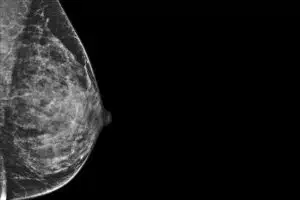

L’examen consiste à prélever une petite quantité de tissu mammaire, dans la zone suspecte, à l’aide d’un repérage échographique ou stéréotaxique (sous mammographie). Le prélèvement est ensuite traité puis analysé en laboratoire par un anatomo-pathologiste, qui identifiera un éventuel cancer du sein et les différents facteurs déterminants pour la prise en charge.

L’indication de réaliser un prélèvement est fonction de la probabilité de cancer. Celle-ci est déterminée en imagerie par la classification Bi-Rads. Ainsi, une biopsie sera proposée aux lésions classées ACR 5 (cancer probable), ACR 4 (cancer possible) et certains ACR 3.

Devant toute lésion non palpable et en cas de chirurgie conservatrice (sans ablation du sein), un repérage est nécessaire, afin de guider le chirurgien lors de son intervention, lui permettant de limiter la taille de l’incision et conserver un maximum de volume mammaire.